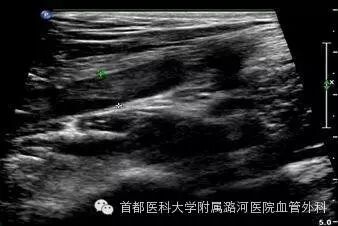

双下肢动脉彩超:考虑右侧髂动脉起始段重度狭窄,余腔内充满低回声。